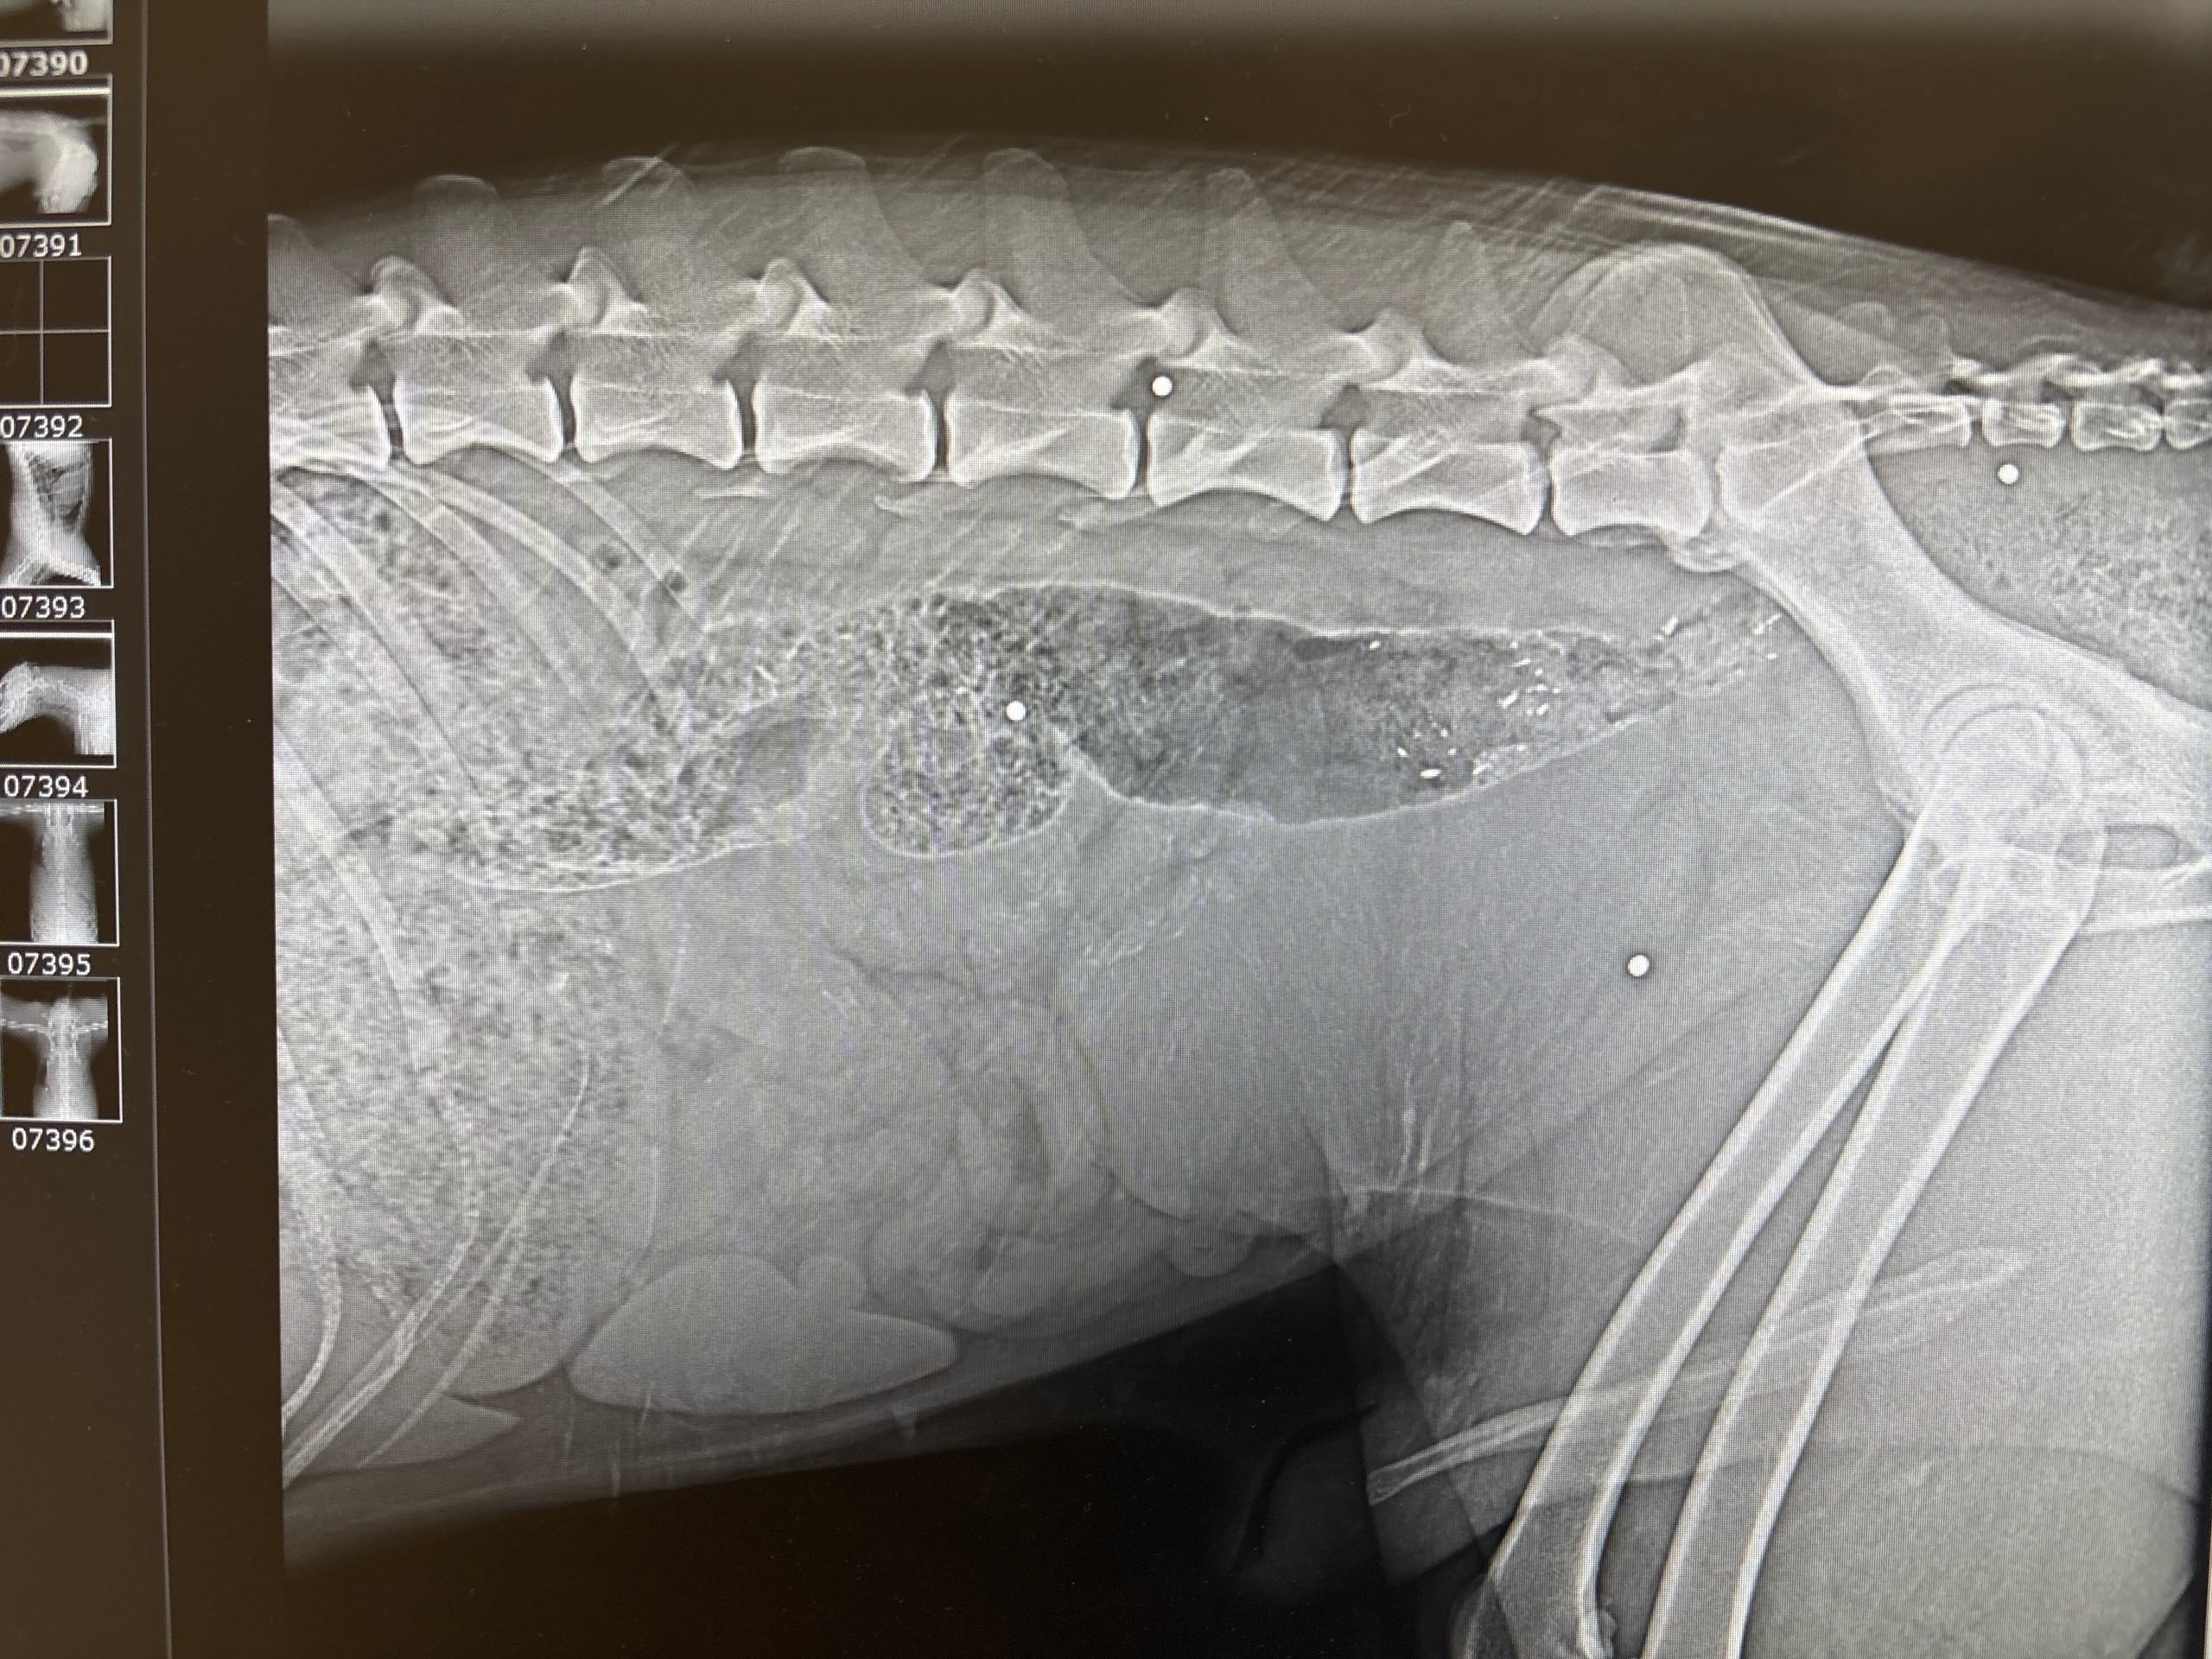

Мужчина по имени Вадим рассказал 78.ru, что отвел своих собак домой, а затем вернулся и при помощи шлейки кое-как вытащил пса, а затем передал волонтерам. Те отвезли его в выборгскую ветклинику, где рентген показал наличие дроби в позвоночнике и мягких тканях.

Позже Вадим нашел еще одну простреленную собаку, сучку, в поле и на этот раз сам отвез ее ветеринарам. И вновь на снимке медики увидели дробь.